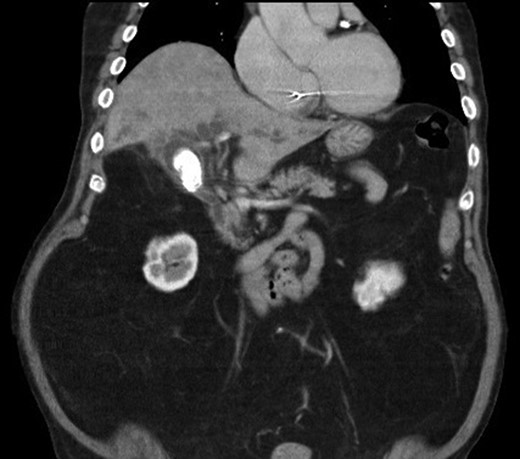

We report a case of a 67-year-old man, who presented with fever, chills and jaundice to a local district hospital. He had a temperature of 39°C and new-onset atrial fibrillation. Examination of the abdomen showed no peritoneal signs. Blood biochemistry demonstrated leukocytosis and abnormal liver function tests: bilirubin 75 μmol/L, alkaline phosphatase 1018 unit/L, alanine transaminase 177 unit/L. Ultrasound scan showed a 3 cm gallstone without common bile duct dilatation. However, computed tomography of abdomen revealed a gallstone eroding into the CHD, causing intrahepatic ductal dilatation (Fig. 1). The diagnosis of type II Mirizzi syndrome was confirmed by endoscopic retrograde cholangiopancreatography (ERCP), where cholangiogram demonstrated a gallstone fistulating into the CHD (Fig. 2). Biliary stent was inserted and intravenous antibiotics were given to tie over this acute episode of cholangitis.

Computed tomography of the abdomen showing a gallstone compressing onto the common hepatic duct.